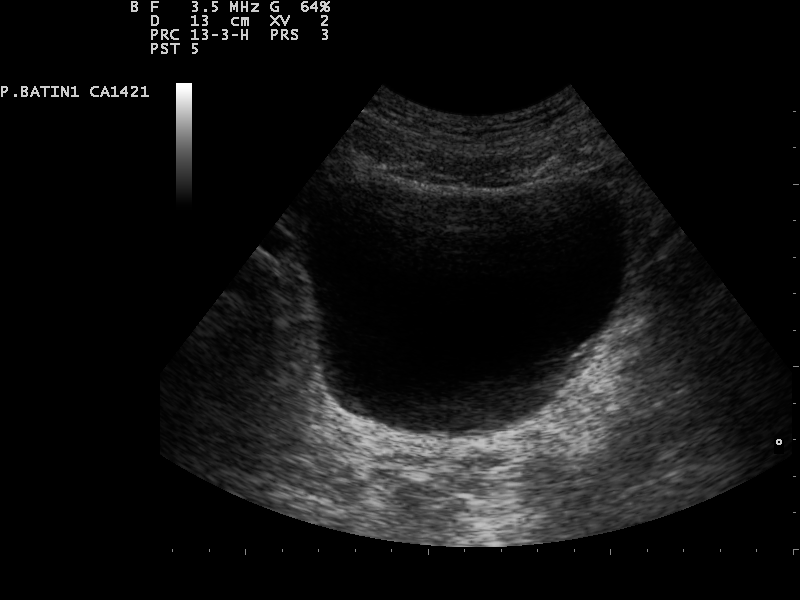

Sonografie der Nieren und Harnleiter

In der Regel wird mit einer Sonografie der Nieren und Harnleiter

Befundung der Niere

- Form: bohnenförmig

- Größe: etwa 10-11,5 cm lang, 5-7 cm breit und 3–5 cm dick

- Echogenität: echoarmes (dunkel/grau) Nierenparenchym, echoreiches (hell/weiß) Nierenhilus

; Nierenbecken und Ureter sind nur im Falle einer pathologischen Erweiterung sichtbar - Nierenvolumen: 100-170 ml (ab 200 ml pathologisch)

- Berechnung des Nierenvolumens in ml

- Formel: V(Niere) = Länge (cm) x Breite (cm) x Tiefe (cm) x 0,5

Pathologie

Neben Raumforderungen, Fehlbildungen (bspw. Hufeisenniere, Beckenniere) ist die Hydronephrose eine mögliche Pathologie der Niere. Sie beschreibt eine Erweiterung des Nierenbeckens und der Nierenkelche infolge einer Abflussstörung. Als Ursachen hierfür können Harnleitersteine, Tumore oder angeborene (kongenitale) Fehlbildungen sein, welche zu einem Rückstau des Urins führen und langfristig die Nierenfunktion beeinträchtigen. Der Schweregrad der Erweiterung (Dilatation) erfolgt in den Graden:

| Gradeinteilung der Hydronephrose | Beschreibung | Sonografisches Bild |

|---|---|---|

| Grad 1 | Echofreie Erweiterung des Nierenbeckens; keine Erweiterung der Nierenkelche | siehe oben Normalbefund bei Sonografie der rechten Niere |

| Grad 2 | Zusätzliche konkave Erweiterung der Nierenkelche | ![]() © Nevit Dilmen, CC BY-SA 3.0, https://creativecommons.org/licenses/by-sa/3.0, via Wikimedia Commons |

| Grad 3 | Konvexe Erweiterung der Nierenkelche und Zeichen der Parenchymatrophie | ![]() © Nevit Dilmen, CC BY-SA 3.0, https://creativecommons.org/licenses/by-sa/3.0, via Wikimedia Commons |

| Grad 4 | Aufgehobene Grenzen zwischen Nierenkelchen und Nierenbecken. Fast vollständige Atrophie | ![]() Nevit Dilmen, CC BY-SA 3.0, https://creativecommons.org/licenses/by-sa/3.0, via Wikimedia Commons |